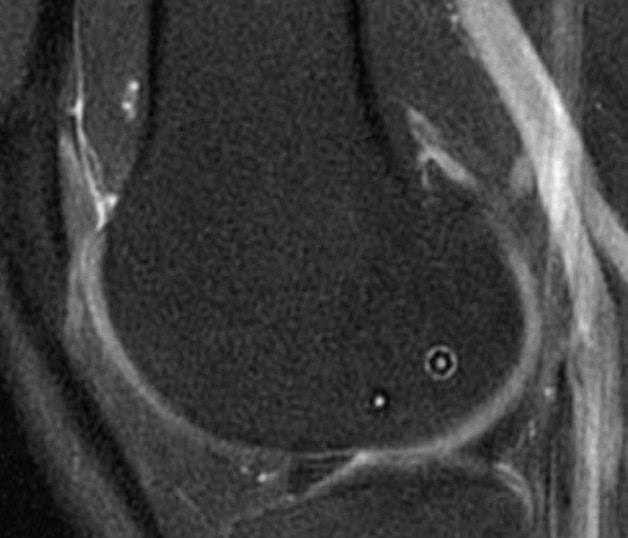

6 Months Post-Op MRI